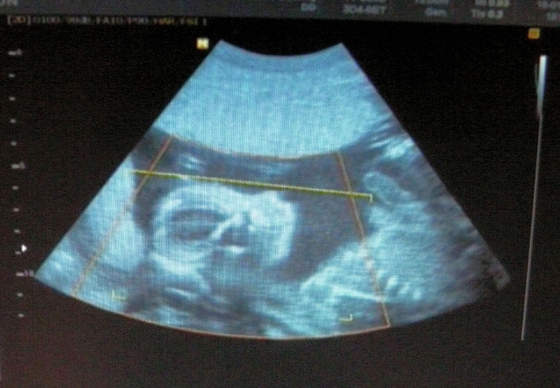

a oto mój synek w połowie drogi :-) (22 tydzień)

może trochę nie wyraźne - ale ja tam widze podobieństwo do męża hihihi